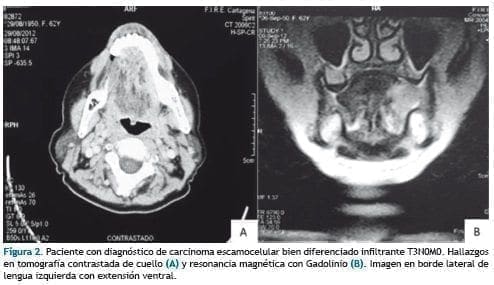

La tomografía contrastada y resonancia magnética simple y con gadolinio, mostraron imagen irregular aumentada de señal en cara lateral izquierda de lengua, captadora de contraste en relación con proceso neo formativo, con normalidad en base de lengua, valléculas y epiglotis, sin imágenes de crecimiento ganglionar. (Figura 2). Los estudios de extensión para metástasis a distancia fueron negativos.

Se estadificó como carcinoma escamocelular de lengua móvil T3N0M0, indicándose Glosectomía Parcial Izquierda, vaciamiento ganglionar cervical de niveles I, II, III ipsilateral y traqueostomia.